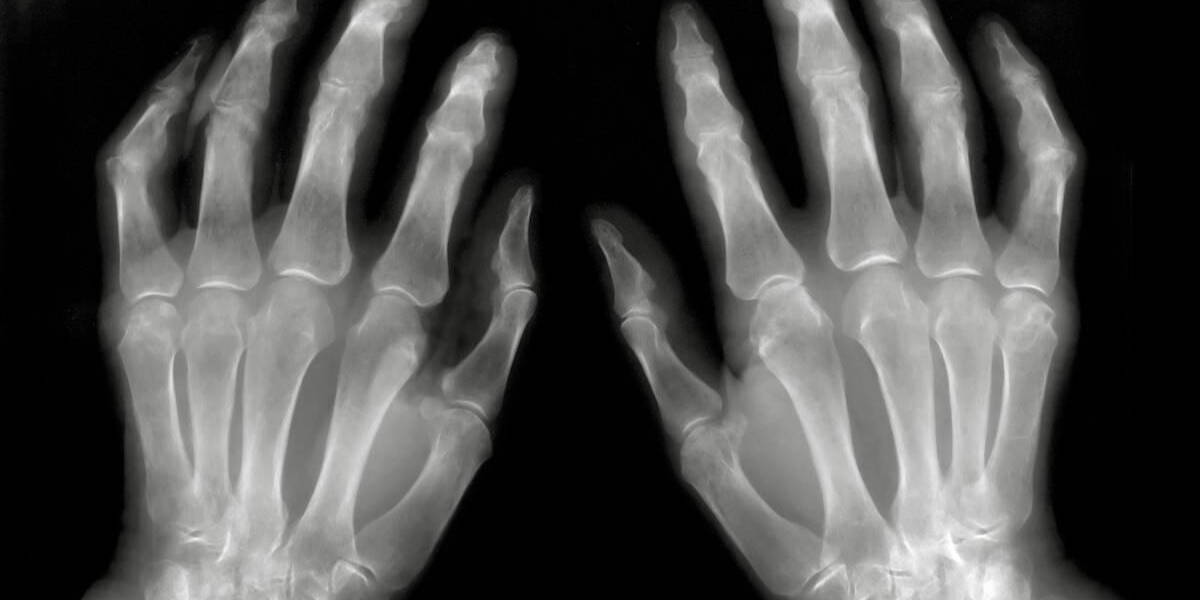

Wetenschappers van het LUMC gaan onderzoeken of kunstmatige intelligentie (AI) kan bijdragen aan het vroegtijdig opsporen van gewrichtsontstekingen op MRI-beelden. Daarbij gaat het om het herkennen van subtiele veranderingen in gewichten van patiënten met reumatoïde artritis. Voor het onderzoek hebben de Leidse wetenschappers een subsidie ontvangen van de Nederlandse Organisatie voor Wetenschappelijk Onderzoek (NWO).

Reumatoïde artritis komt veel voor en wordt gekenmerkt door ontstekingen in de gewrichten van handen en voeten. Er zijn geneesmiddelen beschikbaar die uitgebreide schade aan gewrichten kunnen voorkomen. Voor de meeste patiënten blijft het echter een chronische ziekte waarvoor een langdurige en dure behandeling nodig is.